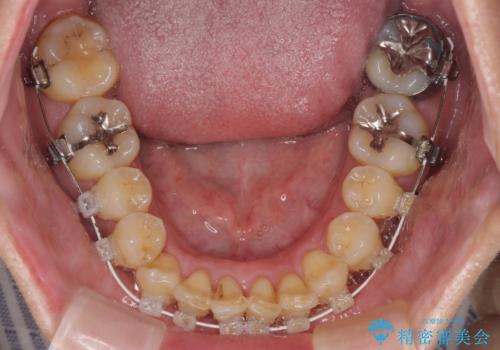

前歯のデコボコ ワイヤー装置での短期間治療

- 前歯のデコボコを気にして来院された患者様です。

インビザラインまたはワイヤー装置、どちらでも対応可能でしたが、自己管理の少なさ、期間の短さから、ワイヤー装置による矯正治療を行うこととしました。

治療開始の頃は、食事や歯磨きが慣れず、装置が頻繁に脱落しましたが、2,3ヶ月ほどで慣れ、その後は1年ほどで治療を終えることができました。